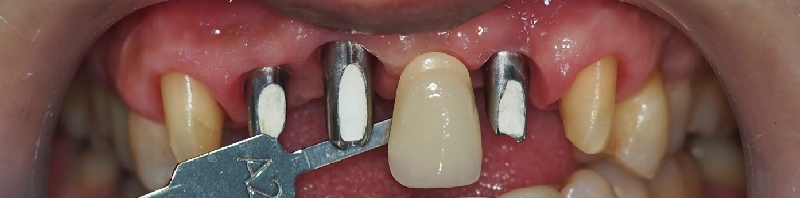

앞니 보철이다 보니 심미적인 부분들도 놓칠수 없는데요.

쉐이드 가이드(치아의 색상과 형태 나열한 판 라고 생각 하시면 됩니다.) 를 이용하여

주변이의 색상과 형태도 맞춰 봅니다.

pmma 라는 최종 보철 전의 수정이 가능한 보철을 임시로

사용해보며 최종 보철을 디자인하게 됩니다.